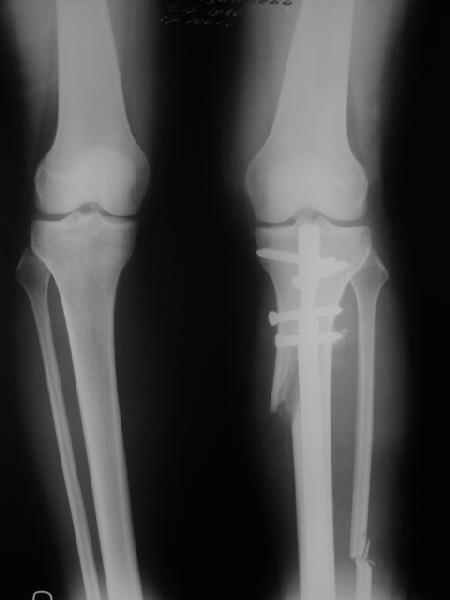

Very nice correction but, to my eye there is some 'over' correction of the tibia, now in some proximal valgus?

Yesterday i performed correction of one leg (the plan to make both in one session was cancelled because of some external reasons). Suggestions of Nuno Lopes were most close to my view. A small wire distractor was used intraoperatively. Derotation ~6-7 degrees was performed also. CT scans evaluating rotation will be available only

tomorrow. No problem to change rotation of the operated limb in the moment of the second surgery. Comments/critics are welcome.

Can the attached result be analyzed by the software?